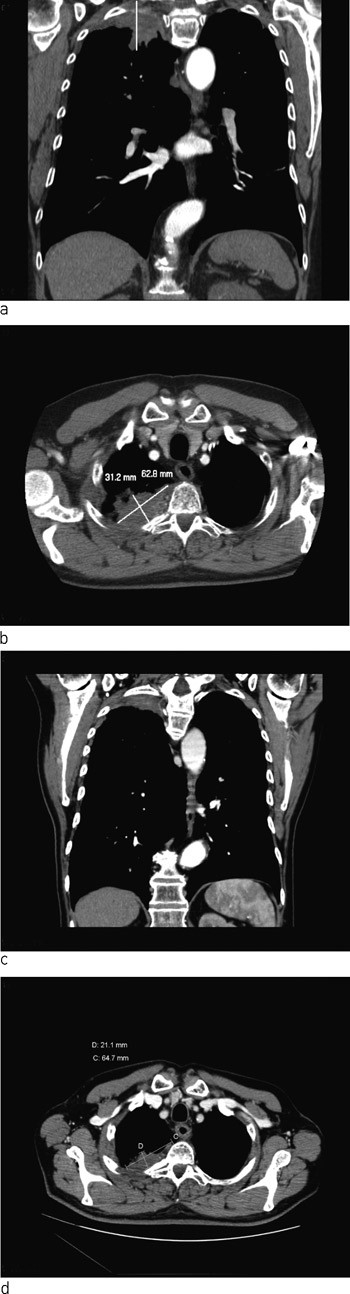

Røntgen thorax (fig 1) tatt rutinemessig ved innkomst viste en oppfylling i høyre lungetopp. CT collum/thorax/abdomen avdekket en ca. 6 cm stor svulst apikalt i høyre lunge (fig 2a, b). Det var ingen tegn til patologisk forstørrede lymfeknuter eller andre svulster. Bildene viste i tillegg emfysemforandringer og et stort abdominalt aortaaneurisme.

Pasienten ble bronkoskopert – uten patologiske funn. Det ble ikke funnet maligne celler ved børstecytologi. Han ble henvist til videre utredning ved Oslo universitetssykehus, Rikshospitalet, hvor CT-veiledet finnålsaspirasjonscytologi viste maligne celler forenlig med ikke-småcellet karsinom. CT thorax viste mulig infiltrasjon interkostalt ved de tre øverste ribbeina, men uten sikker skjelettdestruksjon. MR cervikotorakalcolumna viste at svulsten lå an mot de øverste tre torakale virvler, uten beinaffeksjon, men det ble påvist innvekst i tilgrensende costa.

Fire uker etter avsluttet behandling ble pasienten reinnlagt til operativ behandling med kurativ intensjon. Ny MR collum/thorax viste fortsatt sannsynlig innvekst i 2. og 3. høyre costa samt mulig tumoraffeksjon av Th 2. Det var ikke tegn til affeksjon av plexus brachialis. CT viste at tumor hadde skrumpet (fig 2c, d). Det ble også utført PET-CT (fig 4). Denne var uegnet til vurdering av lokale forhold pga. pasientens nylig gjennomgåtte strålebehandling, men viste ingen tegn til viabelt tumorvev i thoraxveggen eller malignitet andre steder i kroppen. Basert på PET-CT-funnene ble pasienten etter tverrfaglig vurdering bedømt som operabel, og det ble gjennomført lobektomi av høyre overlapp.